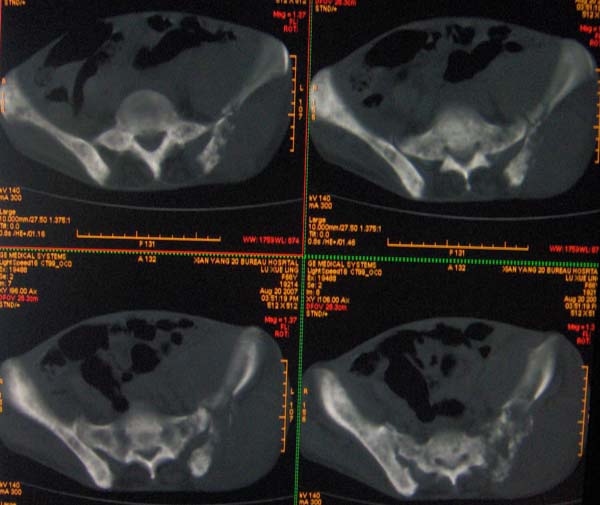

以下是引用ybing在2007-8-22 20:31:00的发言:[br]左侧髂骨溶骨样破坏;软组织肿块形成;其内未见肿瘤骨考虑纤维肉瘤或滑膜肉瘤不除外转移瘤

以下是引用qiushi在2007-8-22 21:39:00的发言:[br]双侧髂骨、骶骨侧快呈溶骨样骨质破坏,边缘模糊,左侧髂骨见骨折线,左侧髂部见软组织块影。考虑骨纤维肉瘤(中央型)伴病理性骨折,不排除骨髓瘤。建议本--周氏蛋白检查。[br] 鉴别点:[br] 骨纤维肉瘤,中央型者示边缘模糊的囊状溶骨破坏,一般无骨膜反映,可膨胀变形,突破骨皮质可形成软组织肿块,或并发病理性骨折。[br] 骨髓瘤,常表现为广泛的骨质疏松,皮质变薄或破坏,呈粟栗状、穿凿状、鼠咬状骨质破坏,边缘清晰,周围无硬化。[br] 骨转移瘤(溶骨型),表现为虫噬样、泡沫状圆形或卵圆形破坏区,很少出现软组织块影。[br][br][本贴已被 qiushi 于 2007-8-23 6:20:19 修改过]